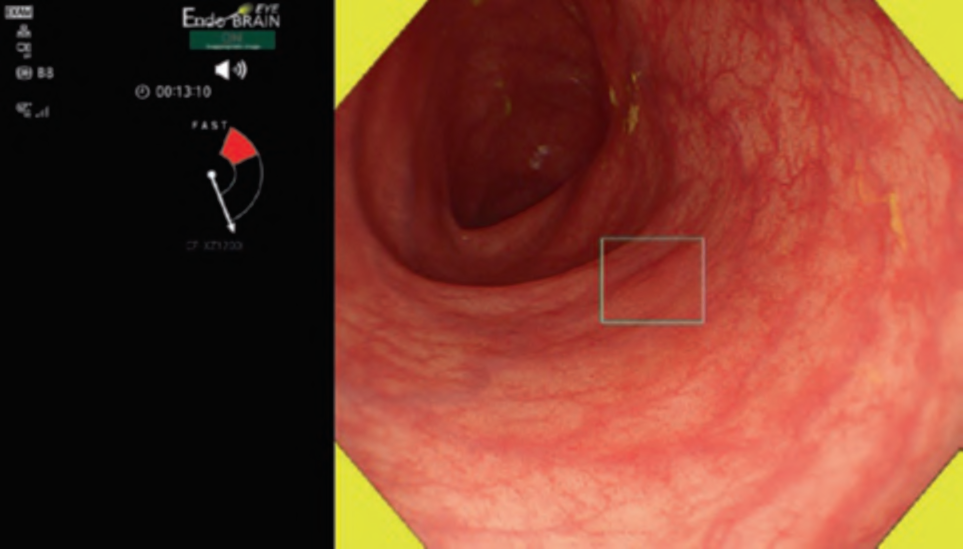

Fig. 1 An example of the computer-aided detection (CADe) in real-time clinical practice. CADe (EndoBRAIN-EYE) detected flat-type lesion by blur rectangle

Corporation and the National Cancer Center), CAD EYE by Fujifilm  Corporation, and EIRL Colon Polyp by L-pixel, all of which have received approval from the Japanese regulatory authorities. . Figure 1 shows an example of the clinical use of the EndoBRAIN-EYE. Looking around the world, numerous other products have been released. Within the scope of our research, several products have been launched on the market as CADe systems, including GI Genius (Medtronic), DISCOVERY (Pentax), Endo-AID (Olympus), MAGENTIQ-COLO (Magentiq EYE), CADDIE (Ordin Vision), EndoScreener (Wision AI), and Skout (ITERATIVE). Among these, GI Genius, EndoScreener, and Skout have become commercially available following approval from the US FDA.